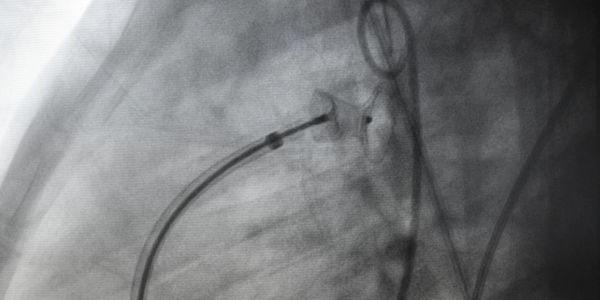

Understanding 3D anatomic relationships with current 2D and 2.5D views poses new and unique challenges, which can lead to procedure complications and inefficiencies as well as create barriers to expand the use of minimally invasive therapies.

EchoPixel overcomes these limitations with a 4D interactive holographic experience that enables real-time accurate situational awareness of catheters and implantable devices in relation to complex anatomy.